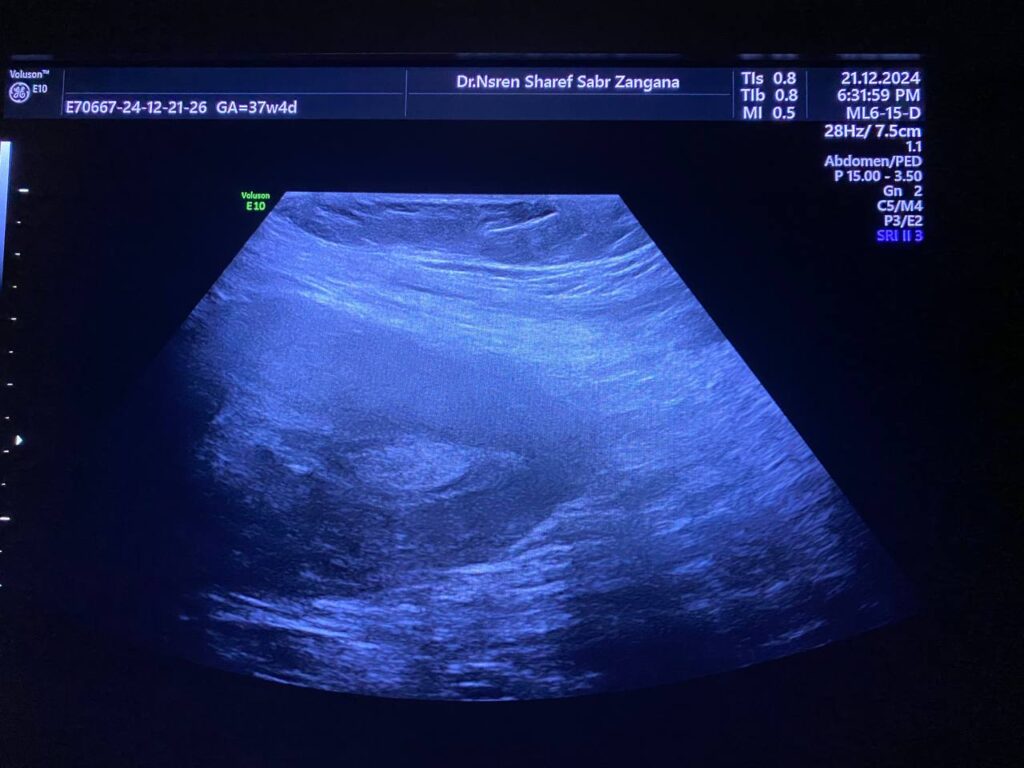

· Left ovary , normal in size , no dominate follicle , with presence of heterogenous vascular solid mass, contain calcification size about 44x30mm with indistinct margin, vascular on color doppler, score 3-4 located just the lateral to the left ovary , with invasion of the adjacent peritoneal & muscular layer ( left rectus abdominis muscle) , mostly suspicious mass , its invasion to the left ovary cannot be excluded , picture could be Desmoid tumor ? peritoneal tumor > , for further study please . no suspicious lymph node seen